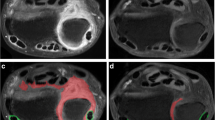

This study aims to characterize patients with early rheumatoid arthritis (RA) based on different definitions of early RA (disease duration, fulfillment of the American College of Rheumatology (ACR) criteria), and to determine whether these different definitions affect magnetic resonance imaging (MRI) findings of the hand. A cohort of 58 patients with early RA previously described was re-evaluated. There were 43 women and 15 men with a median age of 49 years, a disease duration of less than 2 years, and negative radiographs who were followed up for 6–41 months. MR images of the hand and wrist of these patients were retrospectively evaluated for the presence of synovitis, erosions, and tenosynovitis. The presence and distribution of these MRI findings were analyzed in three groups: fulfillment of 1987-ACR criteria, 6-month disease duration, and 12-month disease duration. Median disease duration was 11 months (range 1–24 months). Thirty patients (52%) fulfilled the ACR criteria. More patients fulfilling ACR criteria had MCP erosions and carpal synovitis compared with those not fulfilling the criteria; however, the difference was not significant. No significant difference was seen in the prevalence of synovitis, tenosynovitis, or erosions between the three groups. Patients with early RA of 2-years duration and negative hand X-ray findings are a homogenous group, regarding their MRI findings.